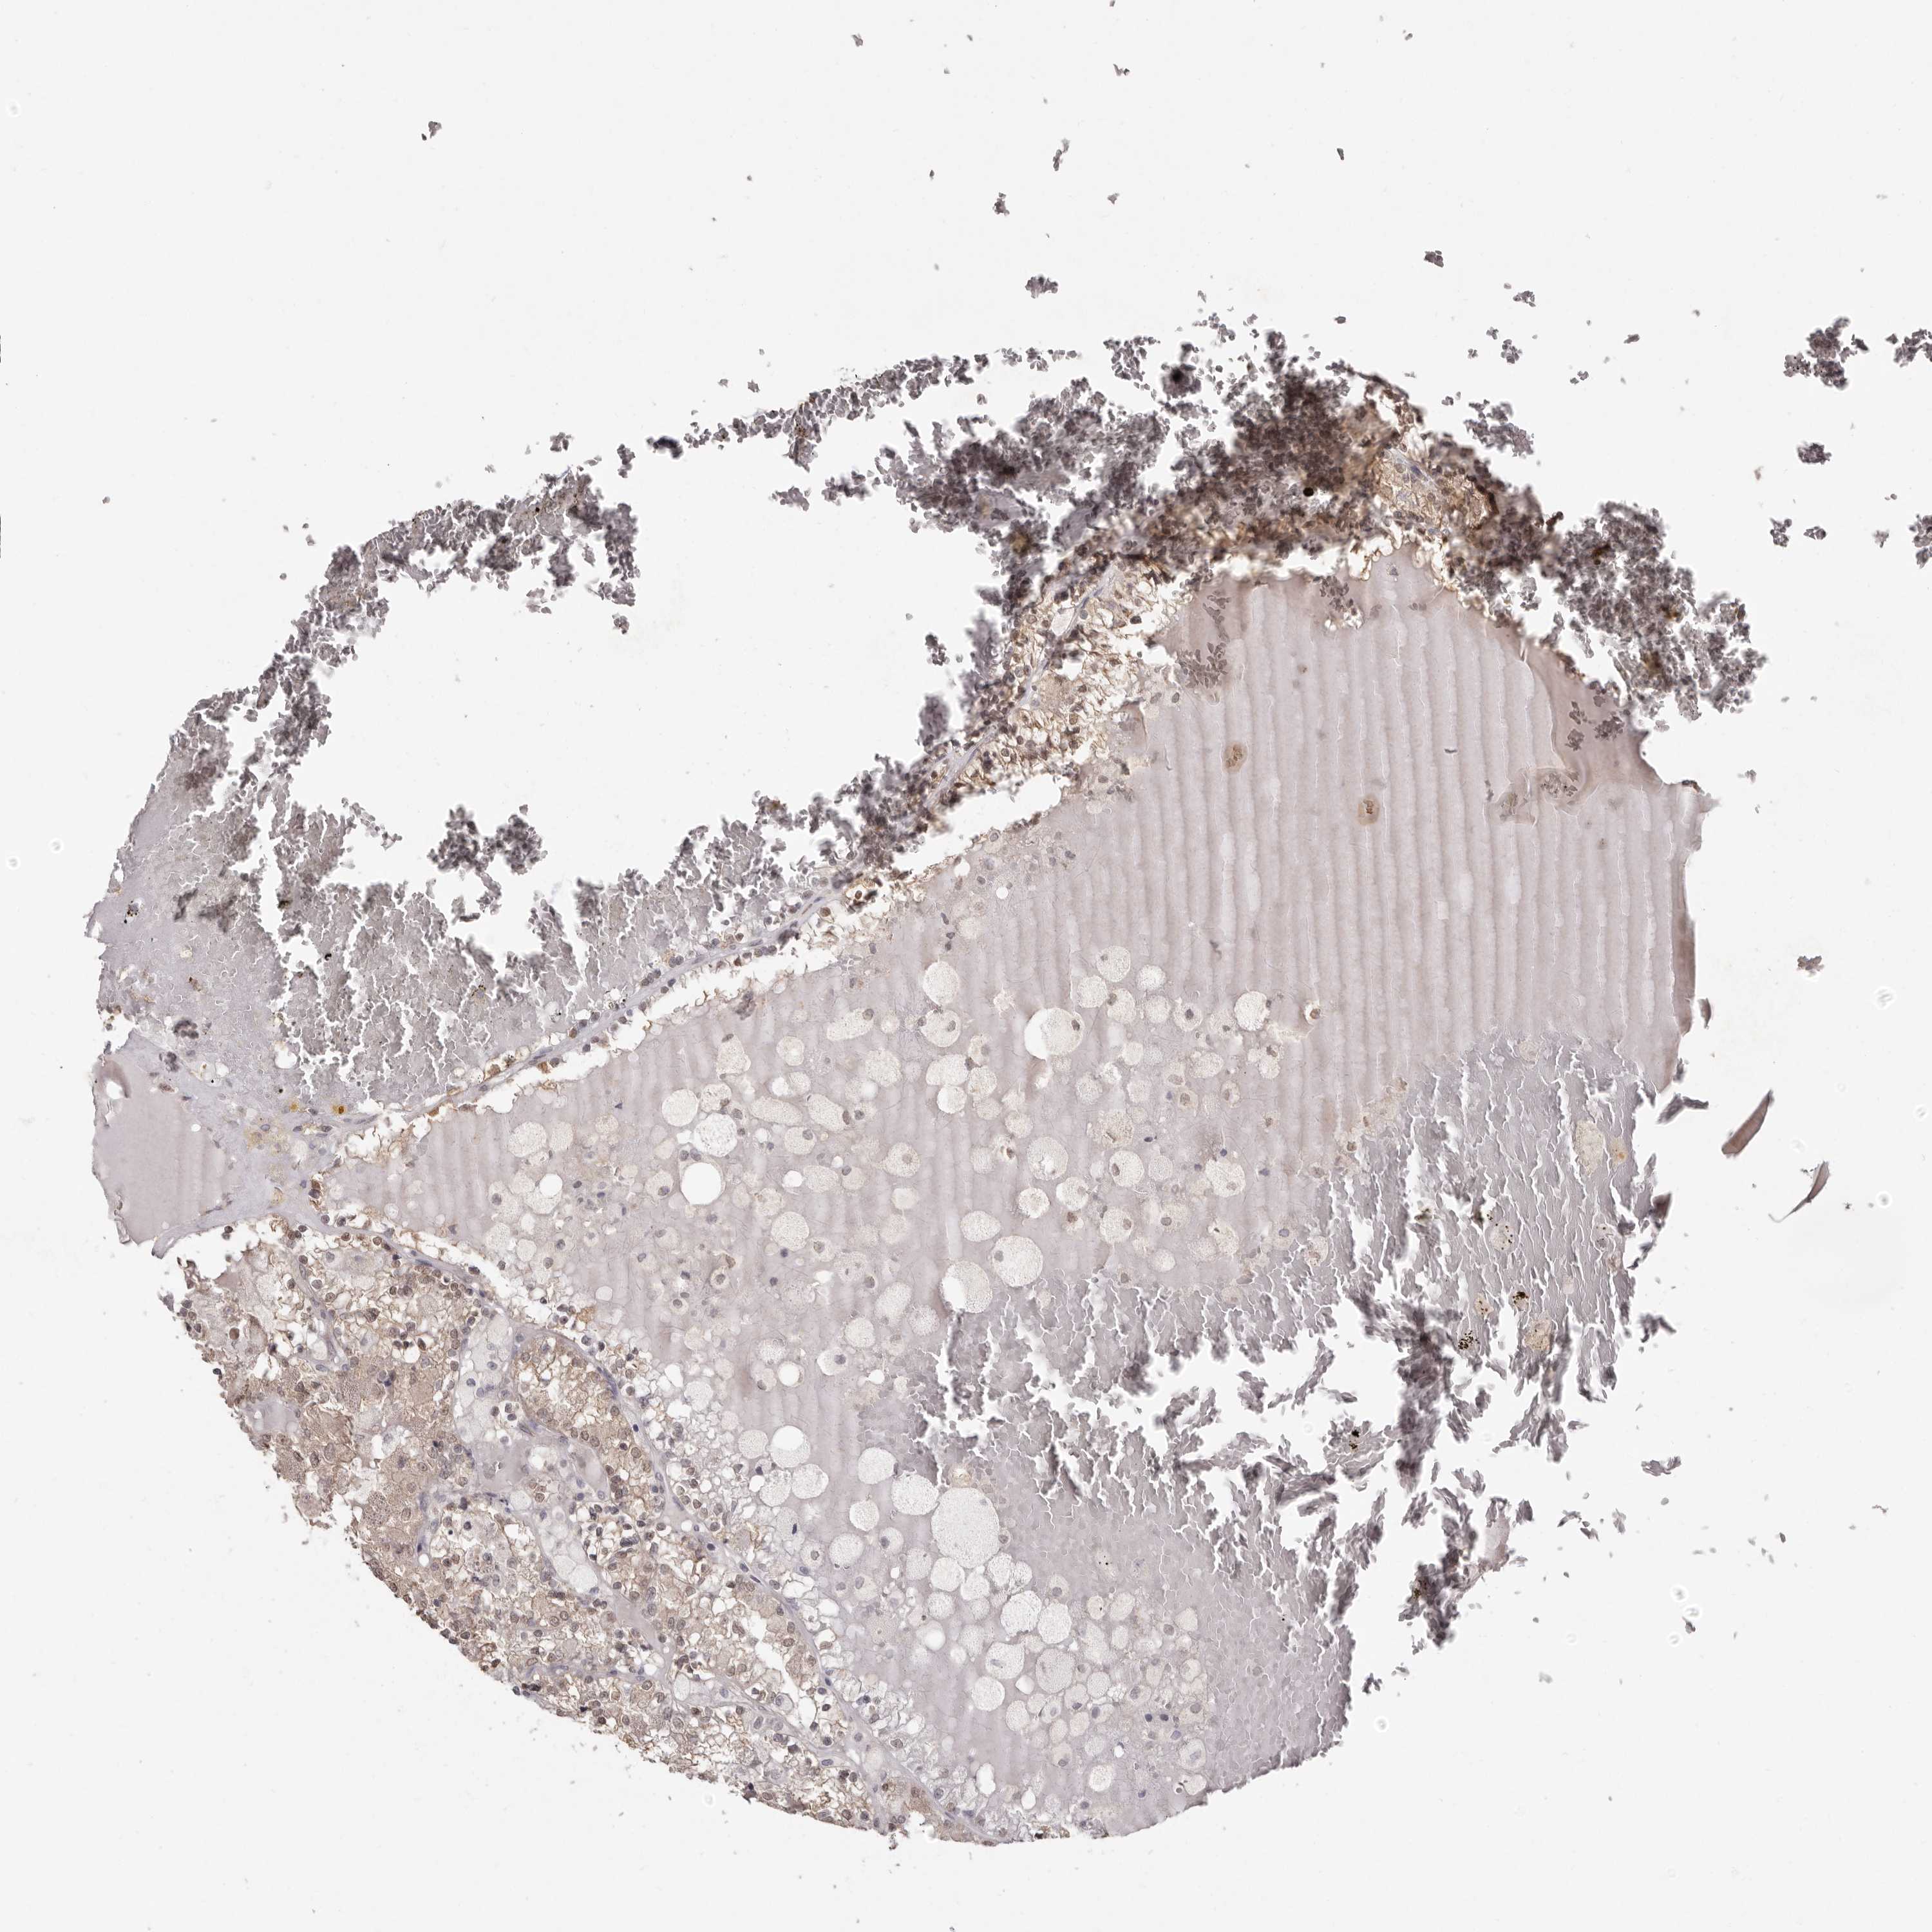

KIDNEY RENAL CLEAR CELL CARCINOMA (VALIDATION) - Interactive survival scatter ploti

The Survival Scatter plot shows the clinical status (i.e. dead or alive) for all individuals in the patient cohort, based on the same data that underlies the corresponding Kaplan-Meier plots. Patients that are alive at last time for follow-up are shown in blue and patients who have died during the study are shown in red.

The x-axis shows the expression levels (FPKM) of the investigated gene in the tumor tissue at the time of diagnosis. The y-axis shows the follow-up time after diagnosis (years). Both axes are complimented with kernel density curves demonstrating the data density over the axes. The top density plot shows the expression levels (FPKM) distribution among dead (red) and alive patients (blue). The right density plot shows the data density of the survived years of dead patients with high and low expression levels respectively, stratified using the cutoff indicated by the vertical dashed line through the Survival Scatter plot. This cutoff is automatically defined based on the FPKM cutoff that minimizes the p-score. The cutoff can be changed by dragging the vertical line or by entering a cutoff value in the square labeled "Current cut-off".

Under the Survival Scatter plot the p-score landscape (black curve; left axis) is shown together with dead median separation (red curve; right axis). Dead median separation is the difference in median mRNA expression between patients who have died with high and low expression, respectively. It is calculated as follows: median FPKM expression of dead patients with high expression - median FPKM expression of dead patients with low expression. This is intended to aid the user in visually exploring custom cutoffs and the associated p-scores and dead median separation.

Individual patient data is displayed and can be filtered by clicking on one or more of the category buttons on the top of the page. Categories describing expression level and patient information include: high, low, alive, dead, female, male and tumor stages. The scale of the x-axis can be toggled between linear and log-scale by clicking on the "x log" button. Mouse-over function shows TCGA ID, patient information and mRNA expression (FPKM) for each patient.

& Survival analysisi

Kaplan-Meier plots summarize results from analysis of correlation between mRNA expression level and patient survival. Patients were divided based on level of expression into one of the two groups "low" (under cut off) or "high" (over cut off). X-axis shows time for survival (years) and y-axis shows the probability of survival, where 1.0 corresponds to 100 percent.

LINGO2 is not prognostic in Kidney Renal Clear Cell Carcinoma (validation)

TCGA RNA samplesi

RNA-seq data is reported as average FPKM (number Fragments Per Kilobase of exon per Million reads), generated by the The Cancer Genome Atlas (TCGA) .

Normal distribution across the dataset is visualized with box plots, shown as median and 25th and 75th percentiles. Points are displayed as outliers if they are above or below 1.5 times the interquartile range. FPKM values of the individual samples are presented next to the box plot.

Average pTPM 0.0

Number of samples 100